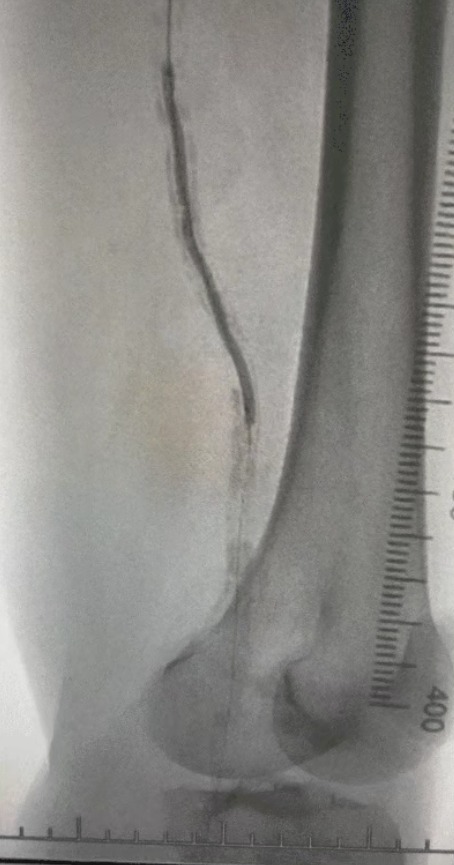

· Предоперационная визуализация: тяжелый диффузный кальцинированный стеноз в двусторонних артериях нижних конечностей.

Хирургический результат

Пост-процедура, артериальный стеноз улучшился значительно, кровоток увеличился, и температура кожи поднялась. Послеоперационных осложнений не произошло. И пациент, и хирургическая команда были очень довольны результатами.